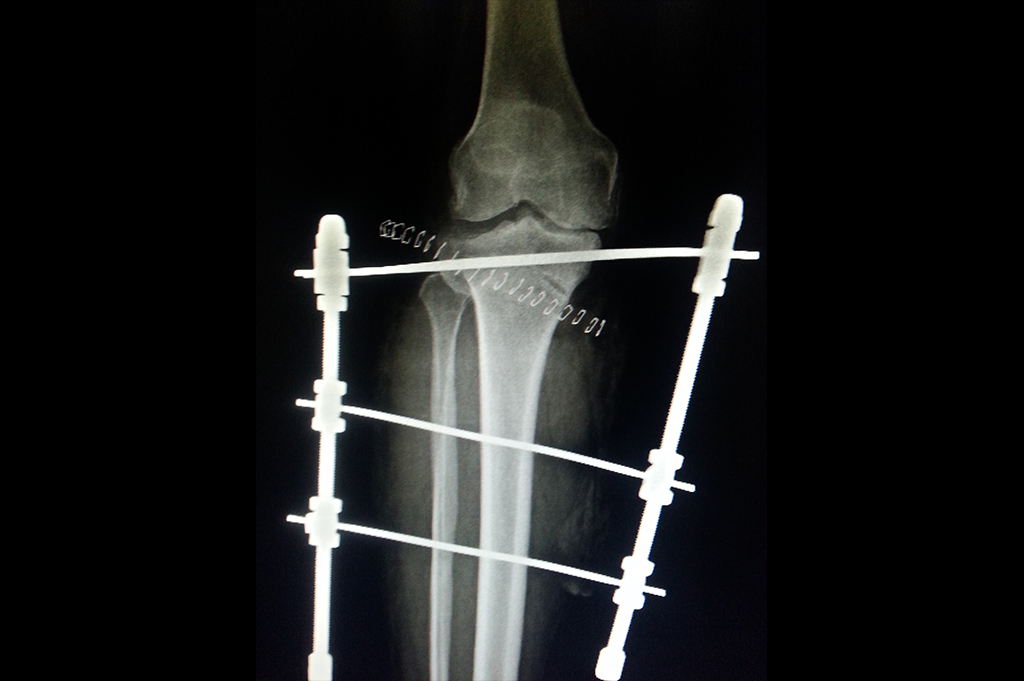

Proximal Tibia